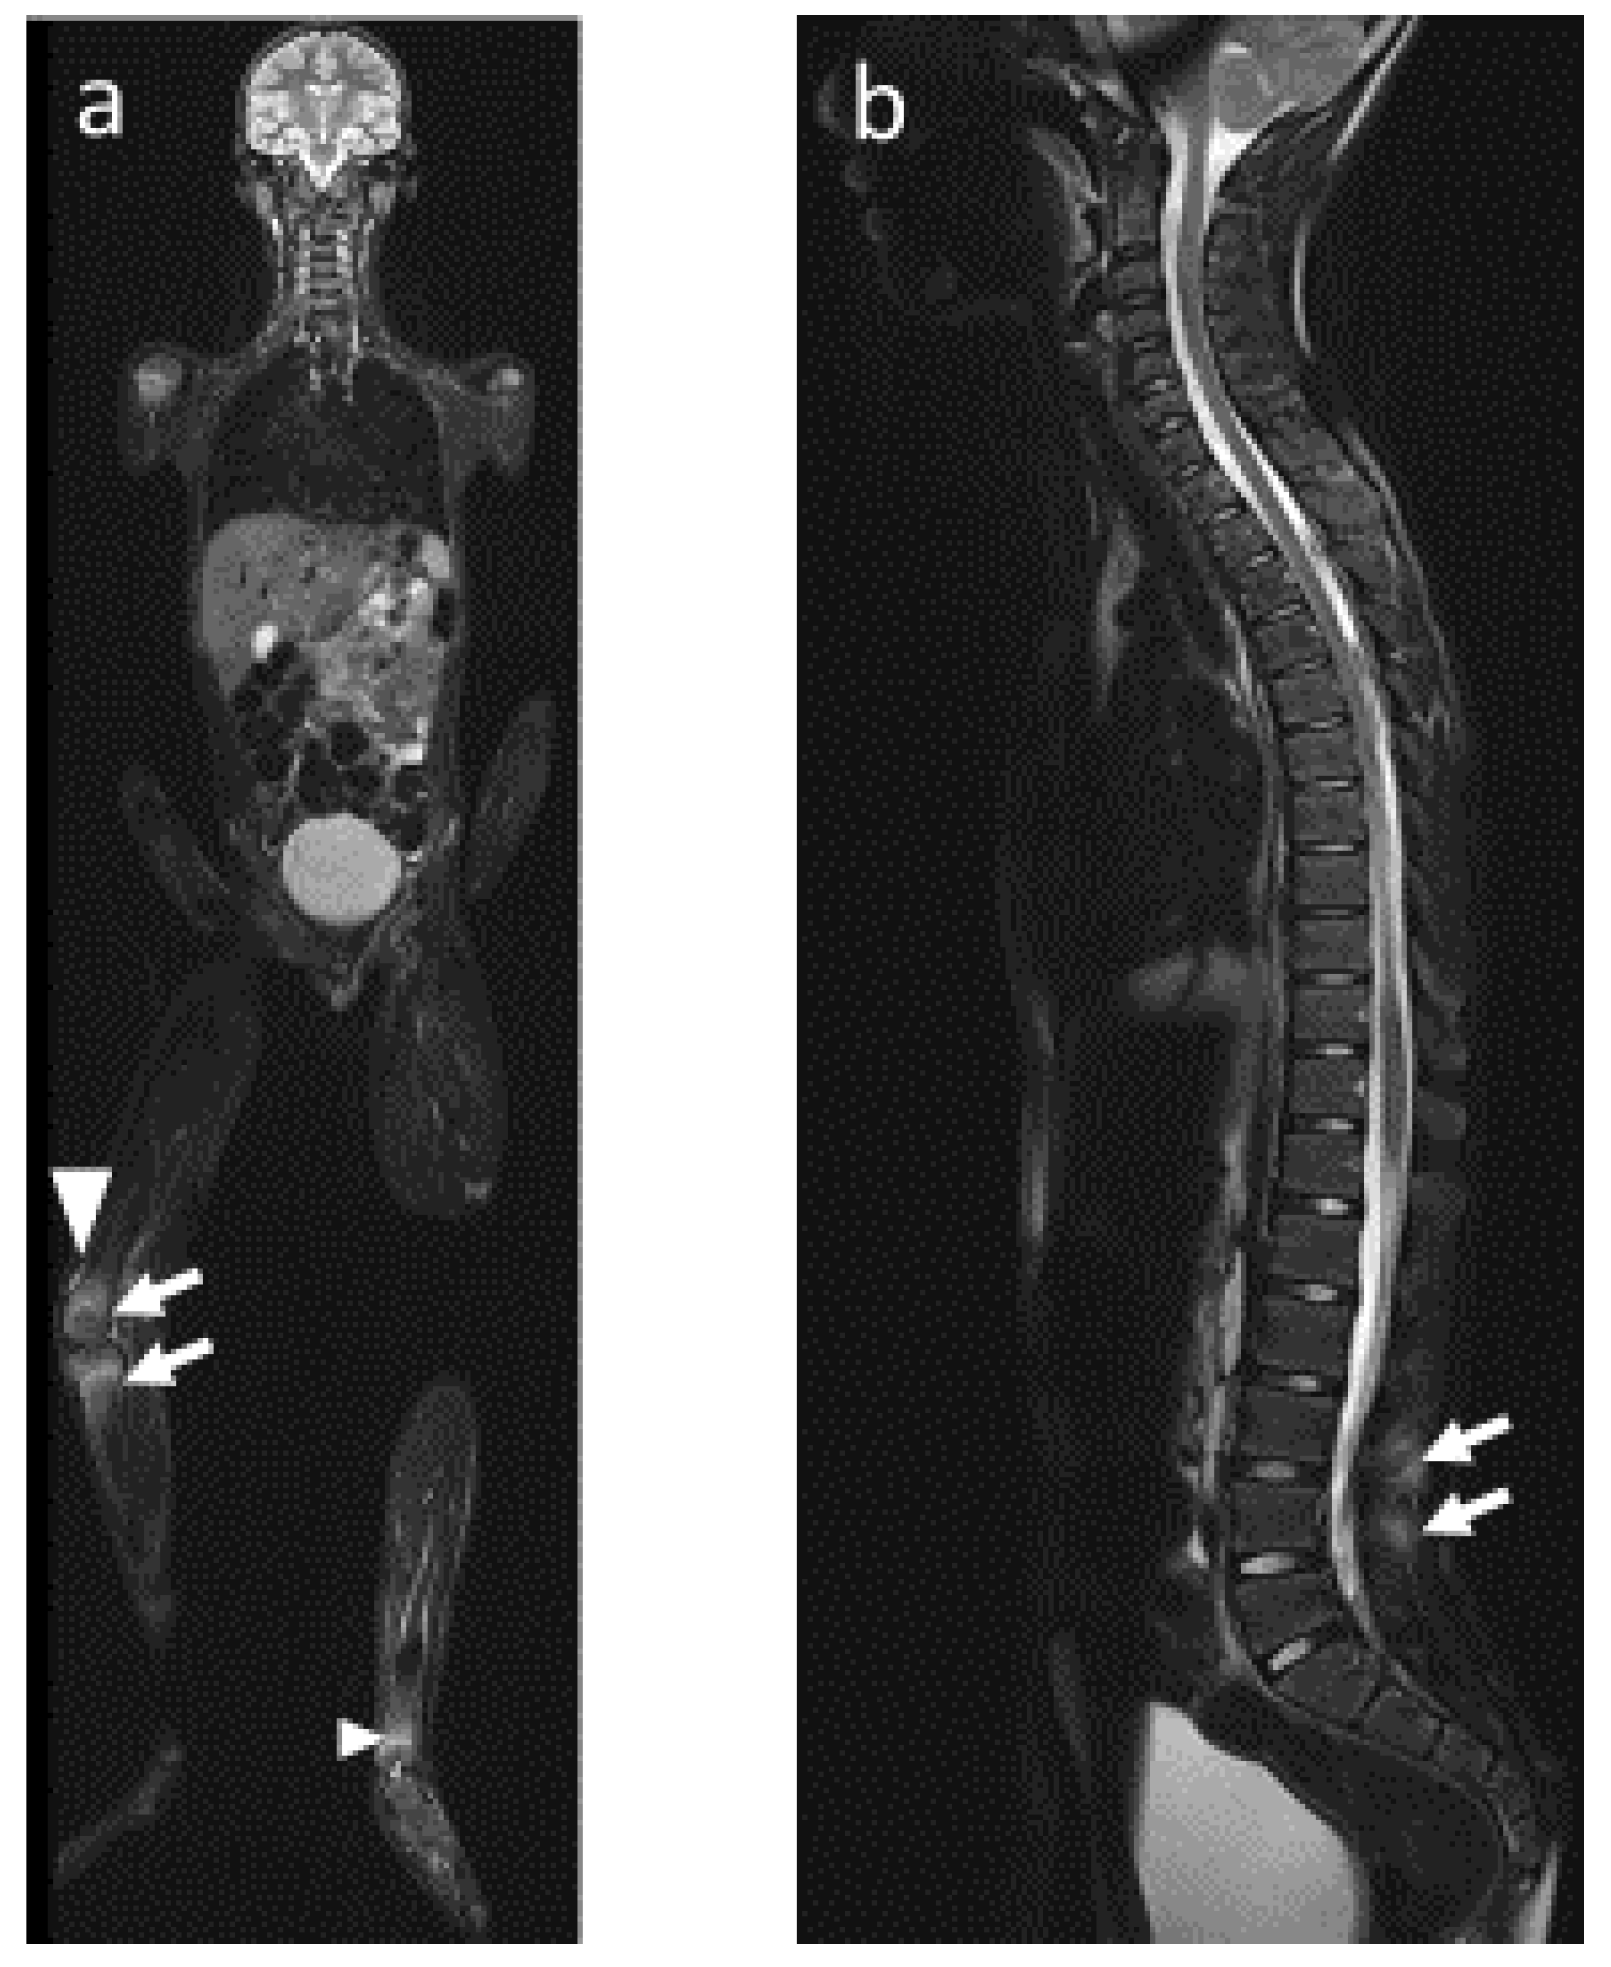

4.2. Radiological Particularities of Each Entity

- (2)

- Vertebral and paravertebral involvement

- (3)

- Sacroiliac involvement